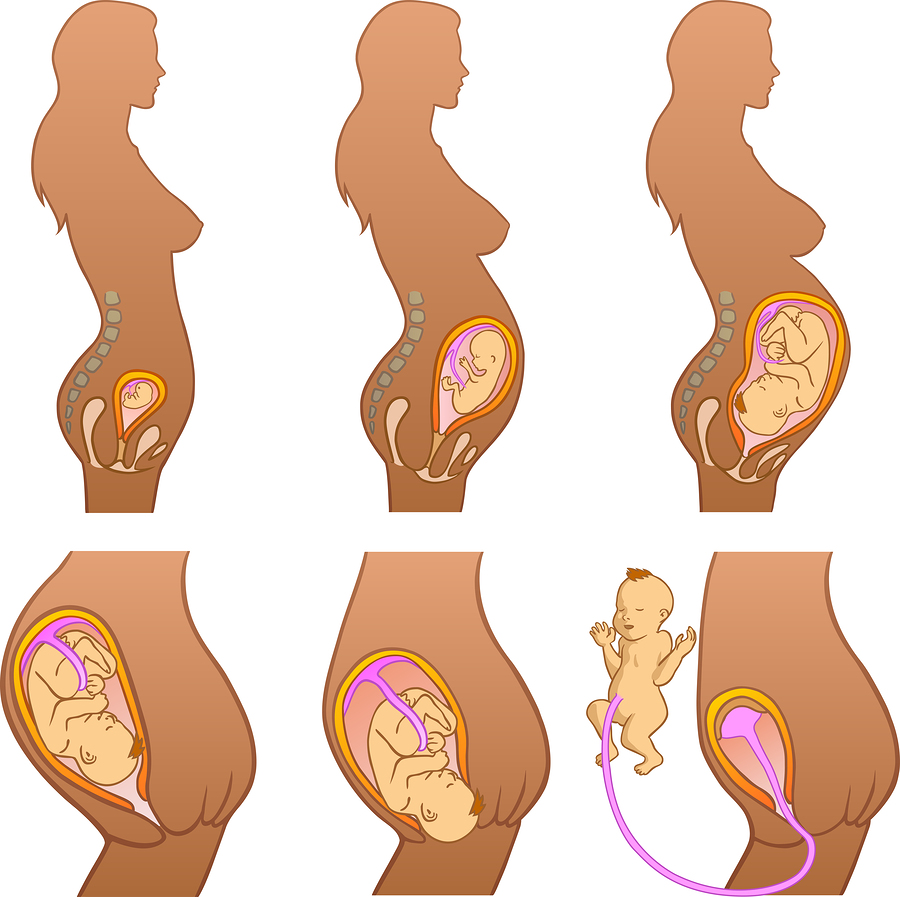

Во время беременности, положение плода имеет большое значение для мамы и малыша. Одним из типичных положений является продольное предлежание головное. В этом положении голова малыша находится внизу, а ножки - наверху. Это положение достаточно распространено и предпочтительно для естественных родов.

Фото положения плода во время беременности

Ниже приведены несколько фотографий, которые помогут вам визуализировать положение плода во время беременности.